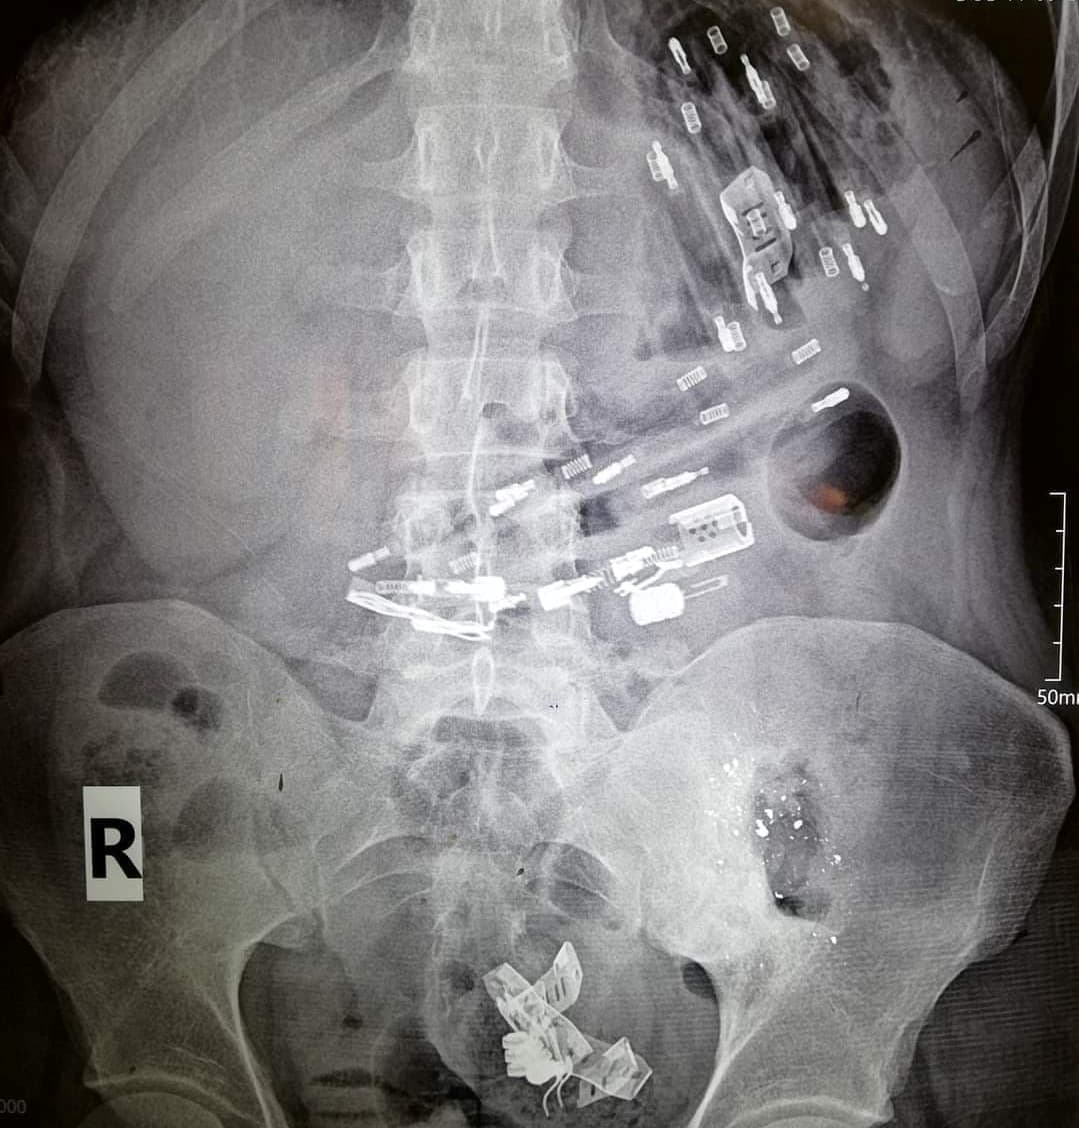

قال الطبيب الجراح علي رمضان العامل في أحد مشافي محافظة الرقة لـ "شام إف إم" إن مريضاً يبلغ من العمر ٢٨ عاماً، راجعنا بشكاية ألم في البطن، وبالتصوير الشعاعي تبيّن وجود عدد من الأجسام الغريبة موزعة في بطنه".

وأشار رمضان إلى أنه تمت عملية استخراج الأجسام الغريبة والبالغ عددها 25 جسماً، تنوعت بين الأسلاك والأجسام المعدنية، إضافة لـ ١٧ "قداحة"، مضيفاً أن المريض حالياً تحت المراقبة الطبية.

وبيّن رمضان أن المريض يعاني من اضطراب نفسي، وكان طبيبه المعالج قد وصف له أدوية مهدئة سابقاً، وسيتم التواصل مع طبيبه ليشرف على الحالة مجدداً.